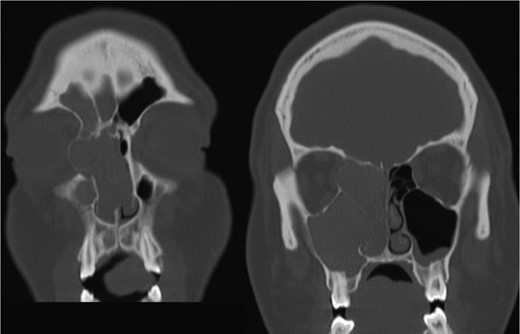

The results of the CT indicated complete opacification of the frontal, ethmoidal, sphenoidal and maxillary sinus on the right side with hyper-dense intraluminal soft tissue filling the sinus cavities. Significant widening of the ostiomeatal complex was observed (Fig. 1). Soft tissue from the right maxillary sinus extended into the right side of the nasal cavity. Extensive changes in the right ethmoidal labyrinth were also discovered. The intact lamella of the middle turbinate and lamella of the bulla ethmoidalis extended further laterally when compared to the left side, and lamina papyracea was protruding into the orbit (Figs 1 and 2). Options were discussed and endoscopic CT guided surgery was recommended.

Axial CT image indicating widening of the ostiomeatal complex with malformation of the right ethmoid.